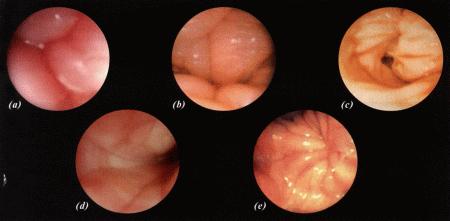

Фиг. 1.3.

Эндоскопическое исследование слизистой влагалища. Динамика изменений на протяжении цикла: (а) проэтрус — розовая окраска и отечность; (b) начало эструса — слизистая бледнеет, отек начинает уменьшаться (обычно перед пиком ЛГ); (c) середина эструса — слизистая бледная, уменьшение отека (сморщивание) явно выражено, что соответствует середине фертильного периода; (d) начало метэструса — видны закругленные складки, при прикосновении слизистая смыкается, образуя розетку (е) (см. Приложение)